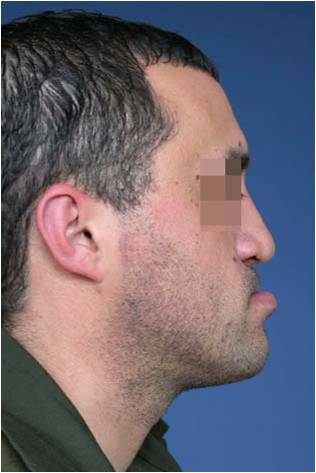

Пациент с недостатъчност в развитието на горната челюст (сагитална максиларна недостатъчност) – преди и след реконструкция на горната челюст - случай на доц. Джоров